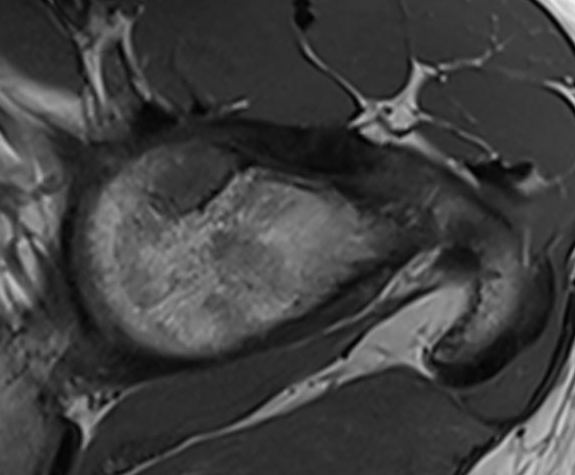

MRI

MR periosteal chondromaMR periosteal chondroma